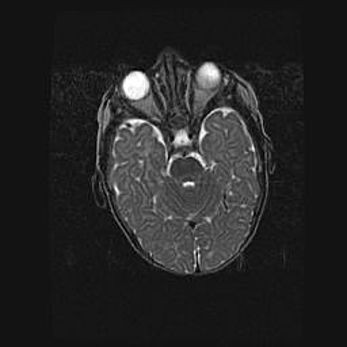

Сообщающаяся гидроцефалия. Кистозная энцефаломаляция головного мозга.

Возраст: 3 месяца 4 дня

Вес: 3100 г

Пол: женский

Окружность головы: 34 см

Срок гестации: 31 неделя

Кистозная энцефаломаляция головного мозга - одна из форм поражения головного мозга в детском возрасте. Характеризуется возникновением множественных и распространённых кист в коре, белом веществе и подкорковых образованиях головного мозга у плодов, новорождённых и детей раннего возраста. Развитие кистозной энцефаломаляции связано с внутриутробной асфиксией и гипотонией, родовой травмой, тромбозом синусов, пороками развития сосудов, инфекциями, сепсисом и другими причинами. Наиболее значимые инфекционные агенты: вирусы простого герпеса, цитомегалии, краснухи, токсоплазмы, энтеробактерии, золотистый стафилококк и другие.